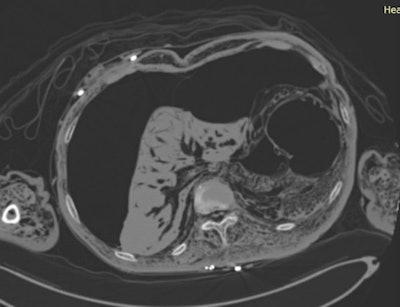

CT image shows severe decomposition of the abdomen.

CT image shows severe decomposition of the abdomen.Boyce: Ultimately in some of those cases, it's a matter of checking that there's no obvious massive trauma if the skeleton is still intact. Sometimes PMCT can help with identification when the police don't know who that person is. We can try to help the pathologist because they don't have to open up the body bag with a decomposed body inside. We can tell them that the person had a pacemaker or a total hip replacement, which enables them to retrieve the device and look at the serial numbers to possibly trace it back. The person might be wearing jewellery, or sometimes the teeth are still intact so we can try to recreate an orthopantomogram to provide a dental image that can be used to identify the person.